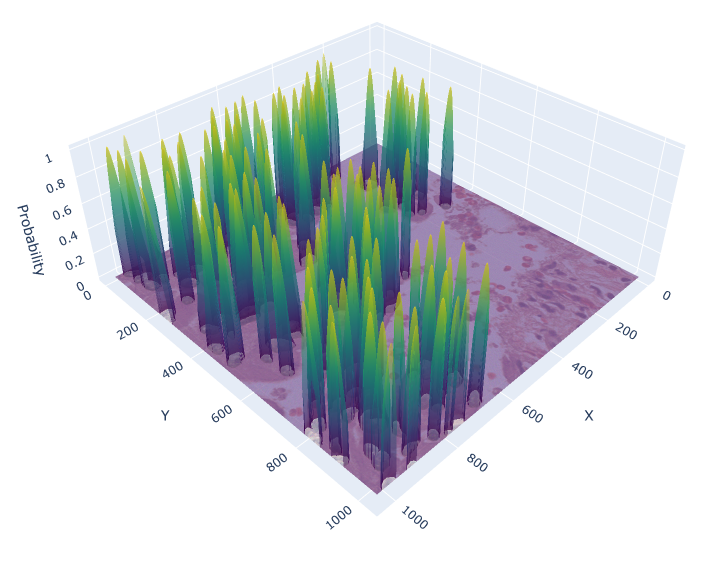

For the circle and soft IS ground truth formats we extract cell detection candidates from the segmentation prediction by applying skimage.feature.peak_local_max on the blurred foreground prediction (Figure 3), where:

Appendix 0.C Ablation study: Different values for soft IS ground truth

The value for soft IS was originally chosen based on a visual review. To investigate, whether there would be a more suitable value, we conducted an ablation study with , analyzing the performance of the soft IS model. Figure 7 shows an example of the soft IS mask for all considered values. The internal train and validation set were used for training and evaluation. The highest mean F1-Score is achieved for , while our initial choice shows a slightly lower performance by -0.6%. Notably, the choice of appears to be a compromise between precision and recall (Table 5). While lower lead to a more precise cell detection, this comes at the cost of a higher number of missed cells (false negatives). The opposite is the case for larger values. Overall, while the difference in F1-Score for and is minor, utilizing for future work is recommended.